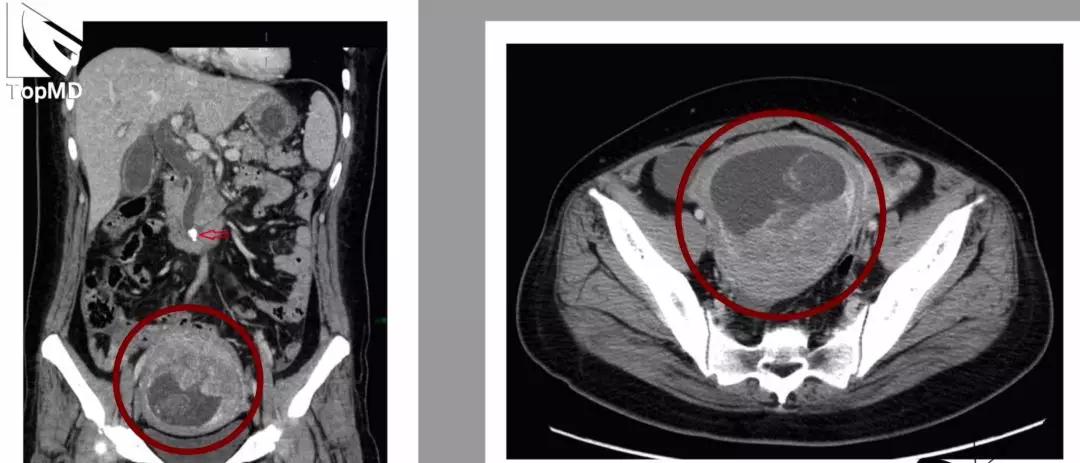

【读片】盆腔肿块——ct平扫,请大家看看!

图片尺寸512x512

ct 显示盲肠附近有一低密度包块,界限清晰(图 1).

图片尺寸640x308